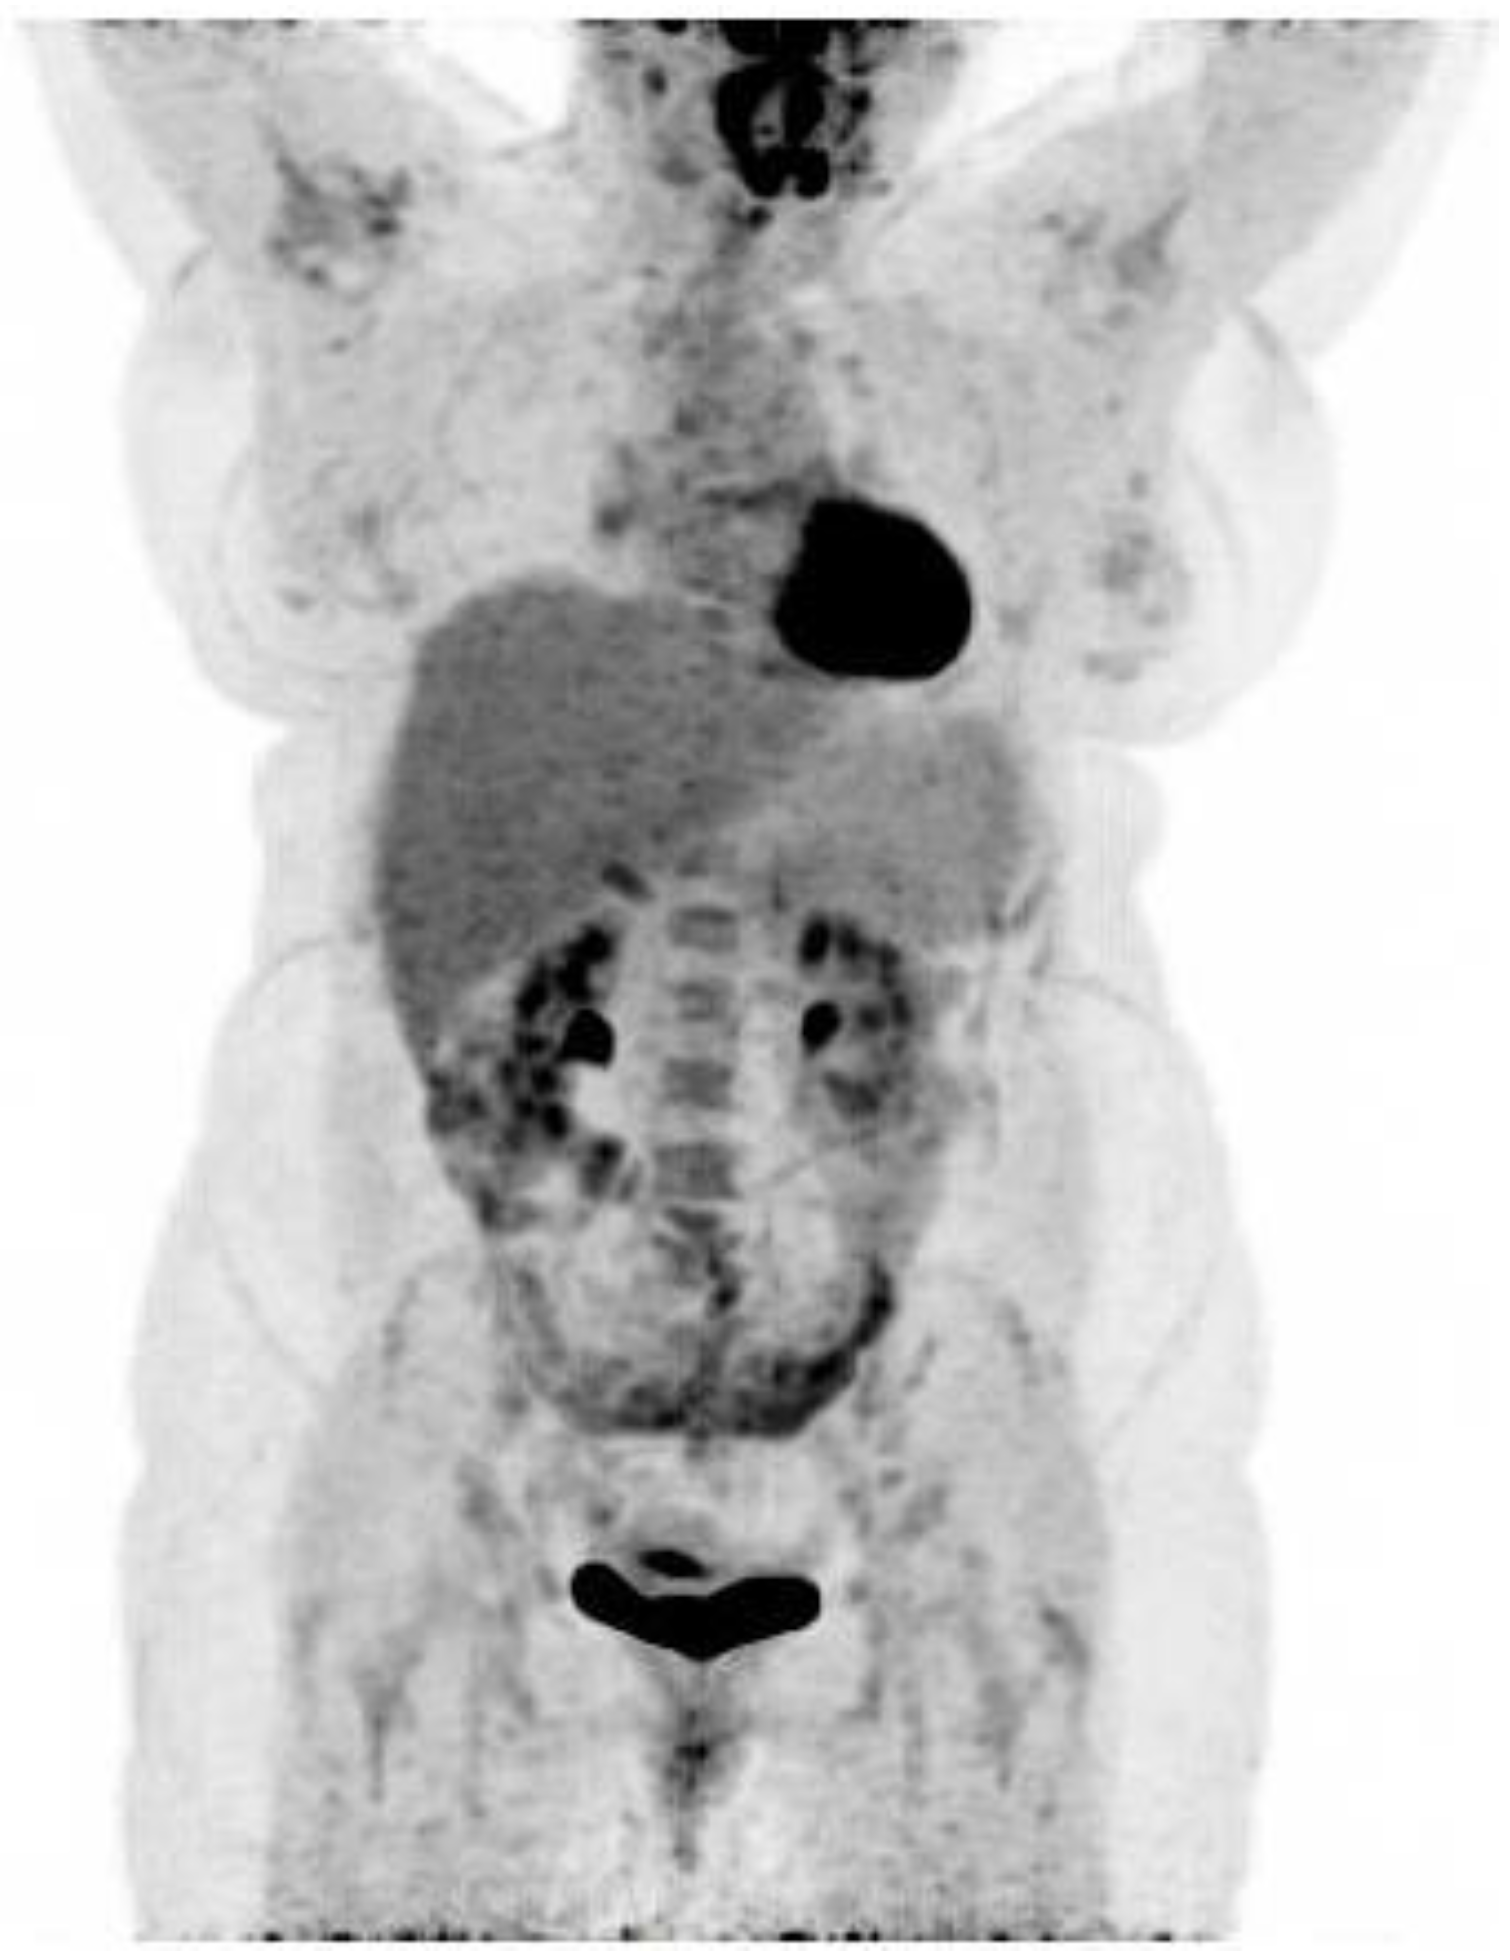

18F-FDG PET/CT Findings in a Patient with Chikungunya Virus Infection